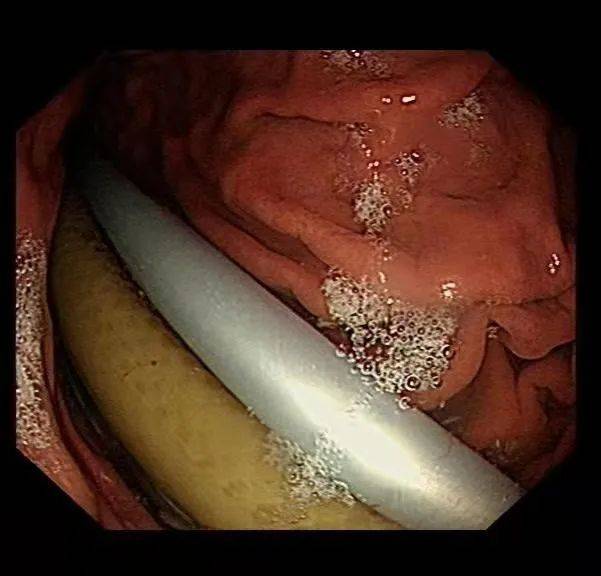

10月29日

经过充分准备

该医院消化内科主任陈正义在麻醉医师

护士的配合下先试行内镜取出

因异物表面光滑且粗大

通过现有器材较难抓取

陈正义便通过

配合使用异物钳、圈套器等

不断调整角度及位置

最终将这几节衣架和塑料管全部取出

使病人免遭开刀之苦